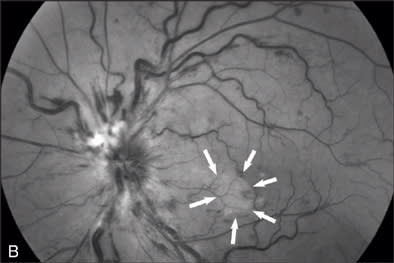

At our initial examination in August 2008, corrected visual acuity was 20/30 in the right eye and 20/50 in the left, with normal ocular pressure in both eyes. There were no rubeosis irides in either eye. Fundus examination appeared normal in the right eye while the left eye revealed a typical nonischemic CRVO (Figure 1A). Fluorescein angiography of the left eye (Figure 1B to 1E) showed generalized dilated, tortuous retinal veins, intraretinal hemorrhages, peripheral retinal non-perfusion areas, and microvascular leakage at the macula (Figure 1E, arrow). Despite the peripheral retinal ischemia, the macula itself was not ischemic at the first visit, as evidenced by the early phase FA showing 2 cilioretinal arteries supplying the fovea (Figure 1C, arrow). Spectral domain OCT (OPKO-OTI, Miami, FL.) confirmed the diagnosis of cystoid macular edema (CME). The patient got intravitreal bevacizumab (Avastin) injection (1.25 mg/0.05 mL) at the first visit.

Figure 1F demonstrates the changes of oximetry between the 2 visits. The arterial oximetry changed from blue to red (red arrow), the venous oximetry changed from green to blue (yellow arrow). The non-perfusion area in the Figure 1F (appeared in blue) disappeared as shown in the follow-up visit report (Figure 2F), this was well correlated with the changes in the FA images in Figures 1D and 2D. The change to the nerve fiber layer infarction area was also observed on the oximetry, where it primarily appeared in white (Figure 1F, black arrow) then it disappeared in the follow-up visit report (Figure 2F), this change was also well correlated with the change between the red-free images (Figure 1B, arrow outlined, and Figure 2B).